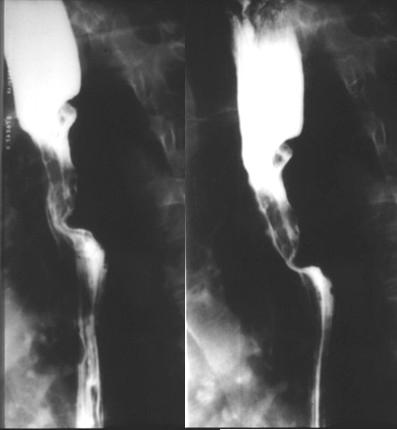

Carcinome epidermoide : stade

avance , extention locale avec deformation maruee le

trajet de oesophage |

Carcinome epidermoide

:Forme ulcero bourgeonnante etendue . La lesion

depasse 5cm |